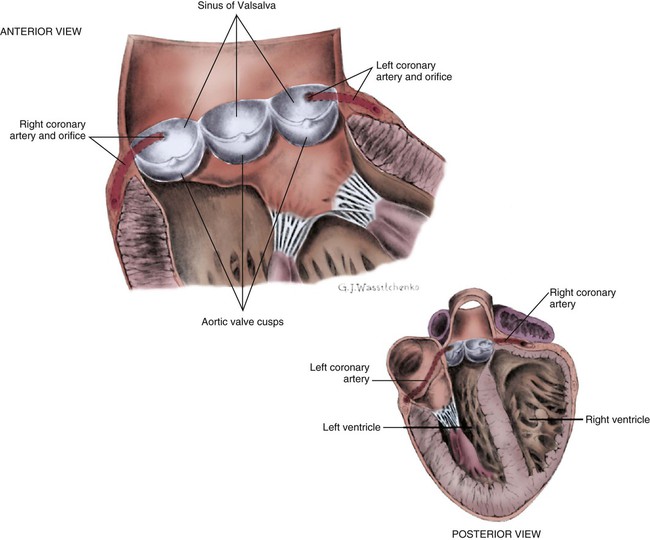

Нормальный диаметр корня аорты: медицинские нормы и отклонения